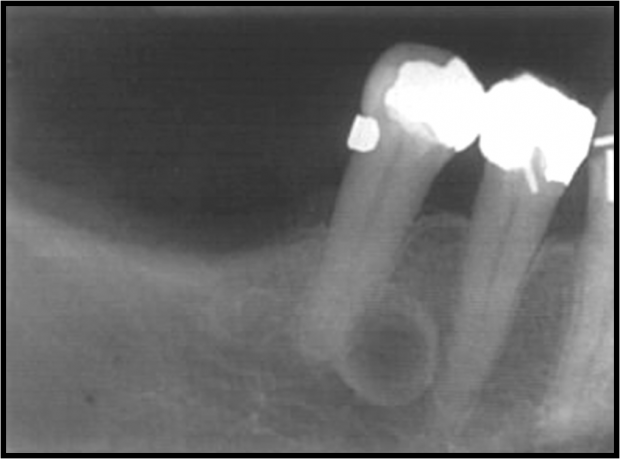

Lateral Radicular Cyst